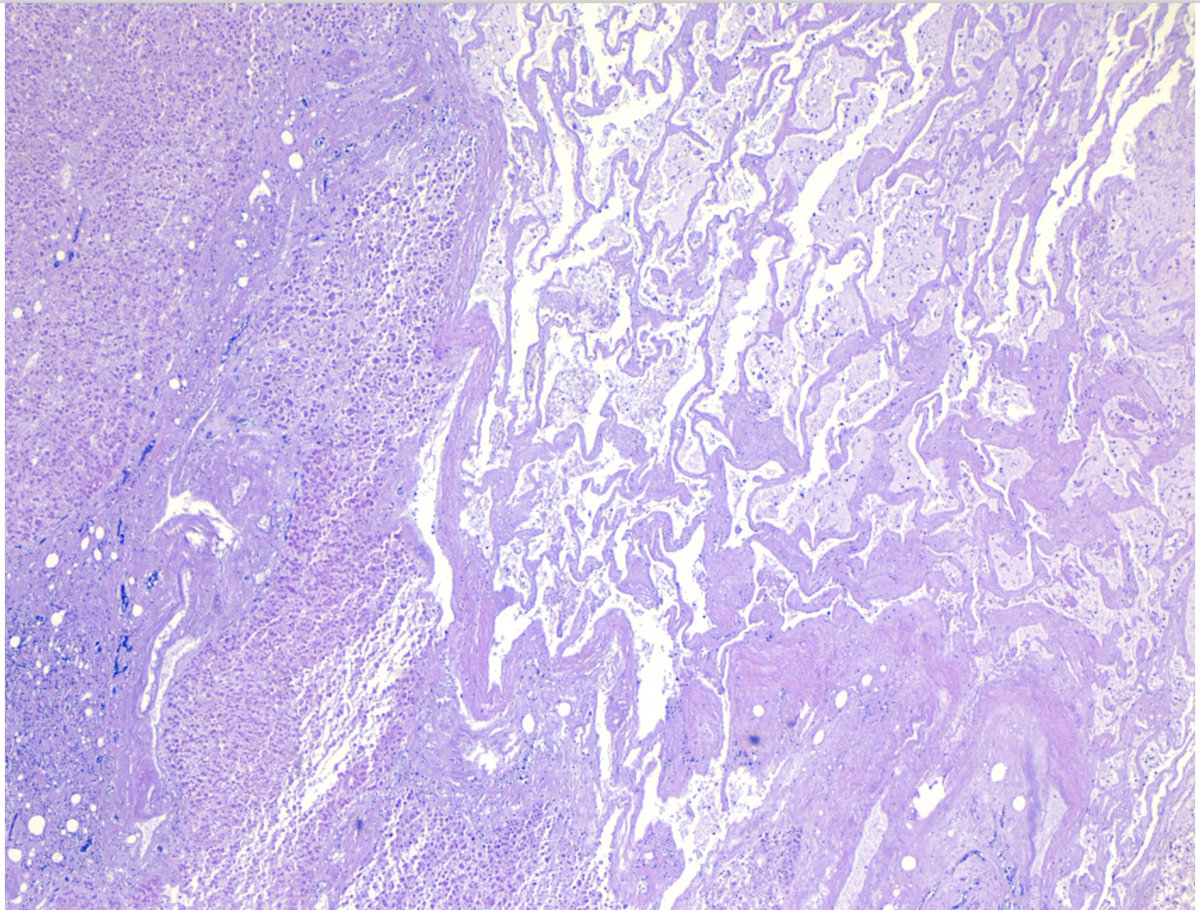

#MTPathUnknown #272

For medical students

What is the organ?

What is the general process (bottom half of image), and what features of the image help you identify the process?

My next YouTube lecture will cover this general topic